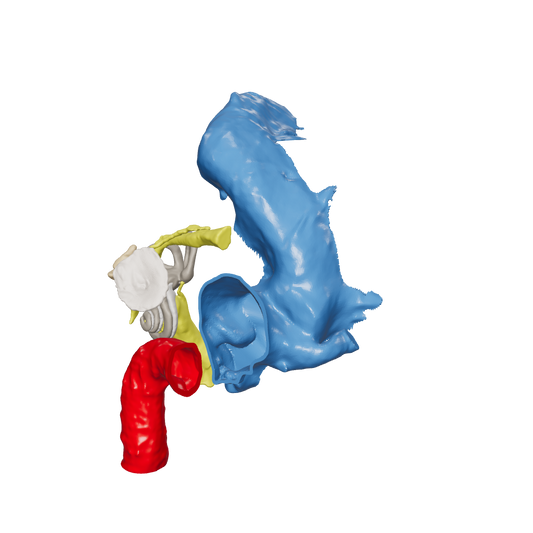

Dissect each one to learn human temporal bone anatomy, hearing and vestibular systems.

*High Contrast Colors* 3D Temporal Bones to Introduce Anatomy (6-pack)

Regular price $402.00 USDRegular priceUnit price per -